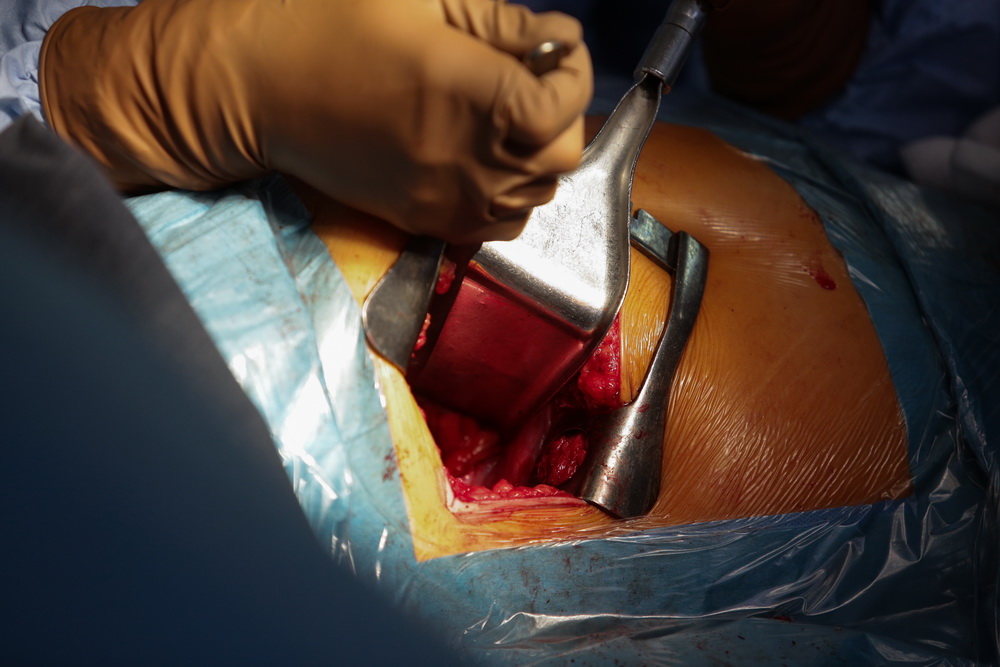

Для сохранения мобильности необходима замена повреждённой части на искусственную. При операции на колене врачи убирают рубцовую и хрящевую ткань большеберцовой и бедренной костей, а в освободившееся пространство как раз и ставят эндопротез. По похожему сценарию имплантатами заменяют и другие повреждённые суставы. Процедура в среднем длится около полутора часов.

Подвижность возвращает операция. В ход идут обычные инструменты ортопедов ― скальпели и пилы. Во время трёхчасовой процедуры хирург удаляет костную муфту, освобождая заблокированный сустав. Операция сложная, задействованы локтевой нерв, трицепс, связки. Всё это нужно не повредить и аккуратно освободить от кости.